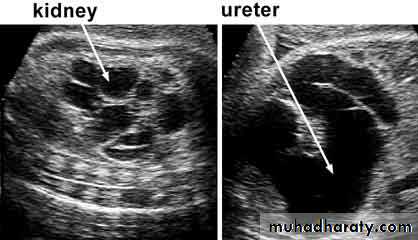

urine cultureImaging of the Renal tract

* Renal U/S* KUB

The goal of imaging studies in UTI is to identify

Anatomic abnormalities that predispose to infection and identify scarring